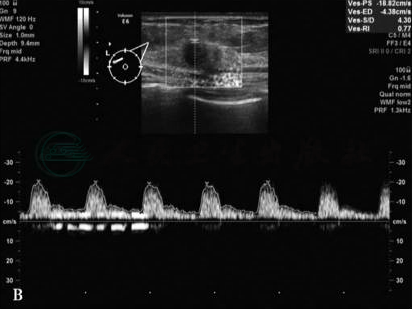

(7)肿块内部及周边血流多较丰富 (图2B);

图2 浸润性导管癌超声图像

A.左乳十点钟方向见一大小约14.6mm×9.5mm×11.4mm的极低回声肿块,呈不规则形,边界不整,内部见散在钙化样强光点,后方回声衰减;B.彩色多普勒血流显像 (CDFI)示肿块周边及内部可见丰富血流